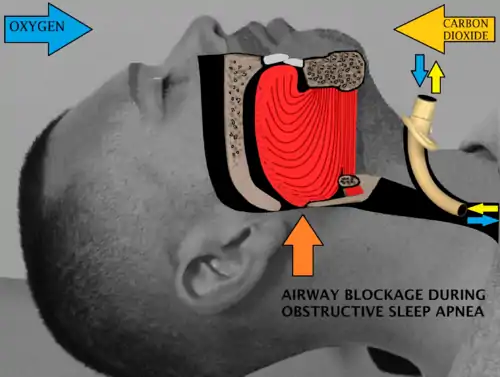

Sleep surgery is a surgery performed to treat sleep disordered breathing. Sleep disordered breathing is a spectrum of disorders that includes snoring, upper airway resistance syndrome, and obstructive sleep apnea. These surgeries are performed by surgeons trained in otolaryngology, oral maxillofacial surgery, and craniofacial surgery.

Definitions

Obstructive sleep apnea or sleep apnea is defined as either cessation of breathing (apnea) for 10 seconds, or a decrease in normal breathing (hypopnea) with an associated desaturation in oxygen and arousal during sleep that lasts at least 10 seconds. In adults, it is typical to have up to 4.9 events per hour. In obstructive sleep apnea, affected individuals are categorized based on how many apneas or hypopneas (apnea-hypopnea index or AHI) or events they have per hour.

- Normal: <5 events per hour

- Mild: 5 to <15 events per hour

- Moderate: 15 to 30 events per hour

- Severe: >30 events per hour